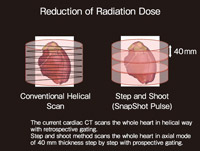

Amazon.co.jp: 心臓CTを活かす 新しい冠動脈疾患診断戦略。心臓CT実践ガイド | 診断と治療社。Vol.5 CTによる心臓検査の有用性と可能性。

Vol.5 CTによる心臓検査の有用性と可能性

心臓CTを活かす新しい冠動脈疾患診断戦略?こういう症例に活用する平山篤志

Vol.5 CTによる心臓検査の有用性と可能性

心臓CTを活かす新しい冠動脈疾患診断戦略?こういう症例に活用する平山篤志